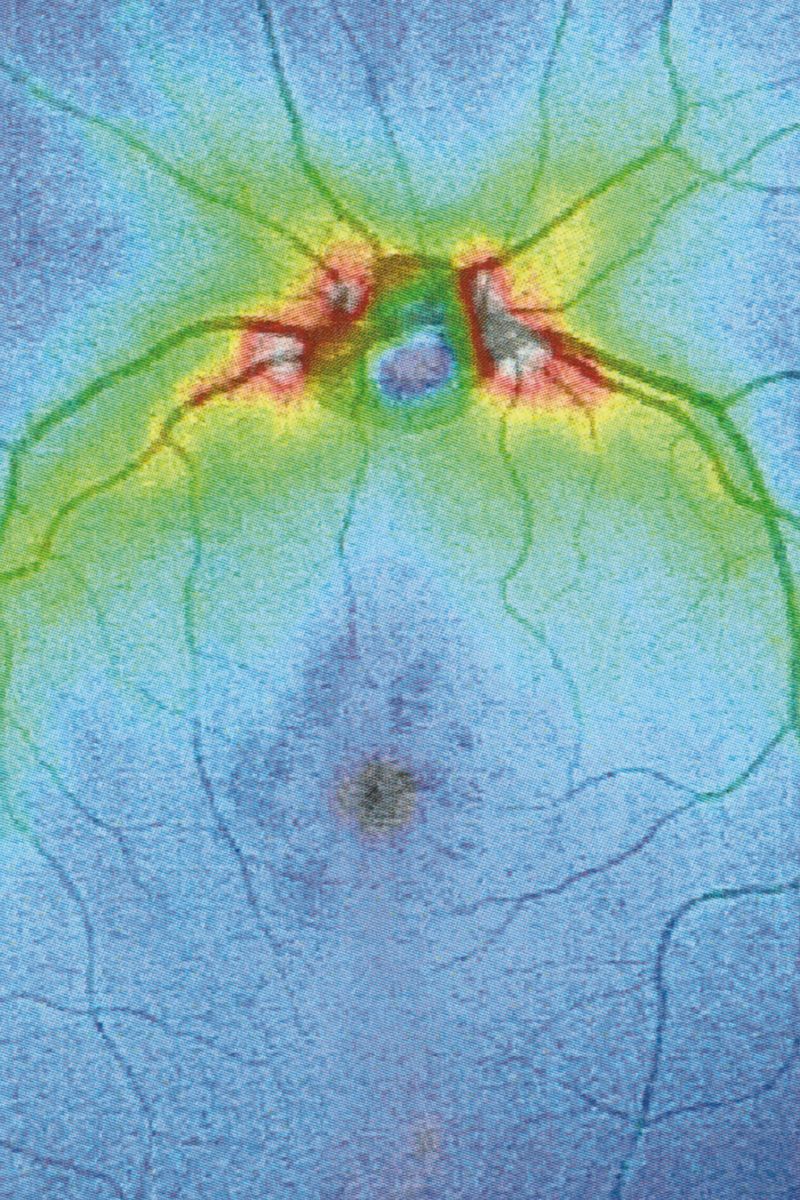

Collirio (Eye wash) is the attempt to demonstrate the non-absoluteness of visual experience, its nature as a situated, and yet, ambiguous act. It is the path that has allowed me to understand how my fears do not have roots in an unknowable place. The eye is not an unfathomable globe.

Collirio is the photographic project I presented for my BA degree at ISIA Urbino. I designed a book (22x29.5cm, 160pages) with text pages and transparent paper inserts and a printed canvas-like dust jacket. A photographic reference scale ruler has been applied on the cover of each of the copies.